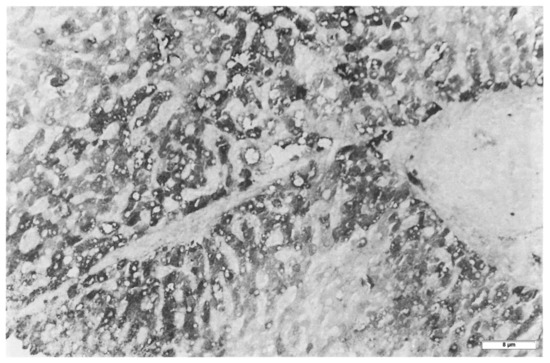

In Groups 1, 2 and 4 biopsies, under the EM, AAT appeared in the form of fluffy amorphous material within the lumen of dilated cisternae of the RER (Figure 8a). In periportal hepatocytes, AAT could also present a more compact, dense appearance (Figure 8b).

Figure 8. PiMZ phenotype patient. The electronmicrophotograph shows a periportal hepatocyte with dilated cisternae of the RER containing amorphous fluffy AAT material (*). RER membranes are in close contact with mitochondria (a) (EM × 15.725). The electronmicrophotograph shows a large cytoplasmic portion of a hepatocyte with diffuse dilatation of ER cisternae. Most of the AAT-like material appears in the form of amorphous semi-electron dense material (*). A few inclusions present a dense, compact appearance and entrapped remnants of disrupted membranes (**) (b) (EM × 7820).